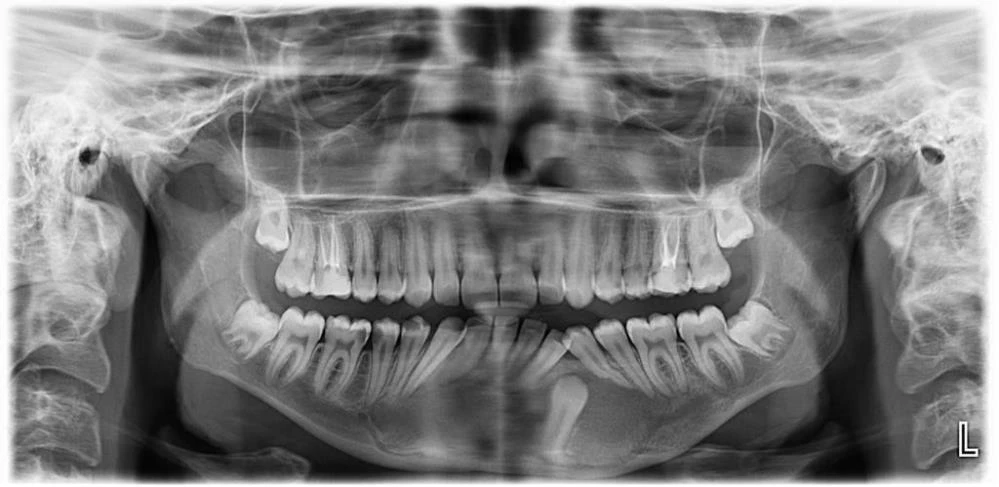

Çene bölgesinde sağdan sola uzanan 7,5 santimetrelik kist için iki aşamalı başlatılan tedavide ilk önce küçültme operasyonu yapıldı. Uzun soluklu takip ve kontrollerin ardından tedavinin üçüncü yılında küçülen kistin alınması için bıçak altına yatan Tuğçe Tüfek, başarılı bir operasyonla sağlığına kavuştu.

Gömülü bir dişle birlikte 7,5 santimetrelik kistin çene bölgesindeki sinirleri ve kemik yapısını etkilediğini belirten ESOGÜ Ağız, Diş ve Çene Cerrahisi Anabilim Dalı Öğretim Üyesi Doç. Dr. Nesrin Saruhan, hazırlıksız yapılacak ameliyatın büyük risk taşıdığını belirtti. Sinirlerde uyuşukluk ve çene kemiğinde kırık oluşmasını engellemek için kist küçültme ameliyatı yaptıklarını belirten Doç. Dr. Nesrin Saruhan, “Tuğçe bize geldiğinde 15 yaşındaydı. Alt çenesinde sağdan sola uzanan 7,5 santimetrelik oldukça büyük bir kisti vardı. Bununla ilgili birkaç merkeze gitmiş ama Eskişehir’de bu tedavinin yapılamayacağı bilgisi verilmiş. Kendisi kliniğimize geldiğinde önce radyolojik muayenelerimizi yaptık. Oldukça büyük bir kist vardı. Hem sinirle ilişkiliydi hem de alt çene kemiğini zayıflatmıştı. Bir de gömülü dişi vardı. İlk etapta parça alıp biyopsisini yaptık. Kist tanısını koyduktan sonra iki aşamalı tedavi planladık. Çünkü mevcut 7,5 santimetrelik kistle ameliyat yapsaydık hem sinirlerde uyuşukluk kalacaktı hem çene kemiğinde kırılma riski oluşacaktı hem de yaklaşık 10 tane dişini kaybetme riski ortaya çıkacaktı. Hastamızın yaşı da küçüktü” dedi.

“İlk etapta kisti küçültme ameliyatı yaptık. Ayda bir kontrollere geldi. Var olan 7,5 santimetrelik kisti oldukça küçük hale getirdik. Böylece kisti hem sinirden uzaklaştırdık hem de alt çenede yeni kemik oluşumunu bekledik. Sonrasında ise genel anestezi ile ameliyatı yaptık. Hem kisti çıkarttık hem de kiste neden olan gömülü dişi çıkarttık. Geri kalan dişlerinde de kayıp yaşamadık. Sinirle alakalı bir sorun da oluşmadı. Uyuşukluğu olmadan dişler ağızdaki yerinde bulunuyordu. En önemlisi de alt çenede hiçbir kırık olmadı ve kendiliğinden kemik oluşumu sağlandı. Kist küçültme tedavileri zaman alabiliyor ama sonuçta hasta daha başarılı bir yöntemle tedavi oluyor. Hem hekim hem de hasta için oldukça iyi bir tedavi protokolü olmuş oldu. Bu tip durumlarda hastaların korkmamaları ve ilerlemesini engellemek adına mutlaka yapılması gereken oral patolojileri yaptırması gerekiyor.”